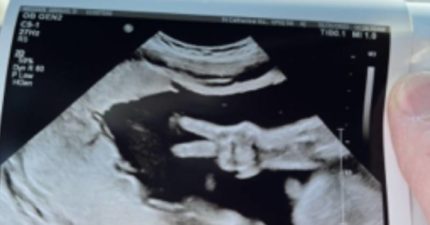

奇蹟瞬間!媽媽照超音波「寶寶肚中比YA」 爸爸傻了:當時突然就有2隻手指頭伸出來

February 6, 2023

世界, 親子